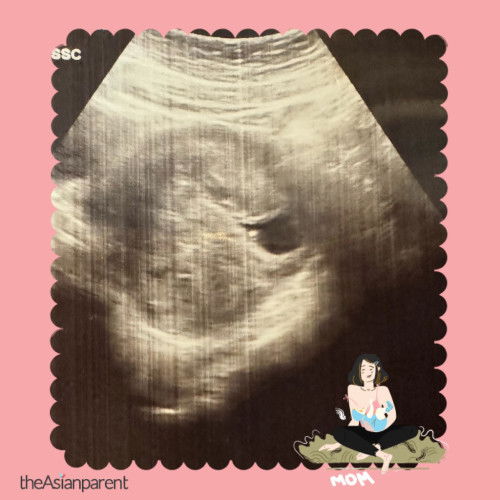

#pleasehelp scan di bawah 10w

Masa sis scan ni doktor xde ckp apa2 ke sis?

Delay misscarriage, rahim dah kecut 😔😔😔